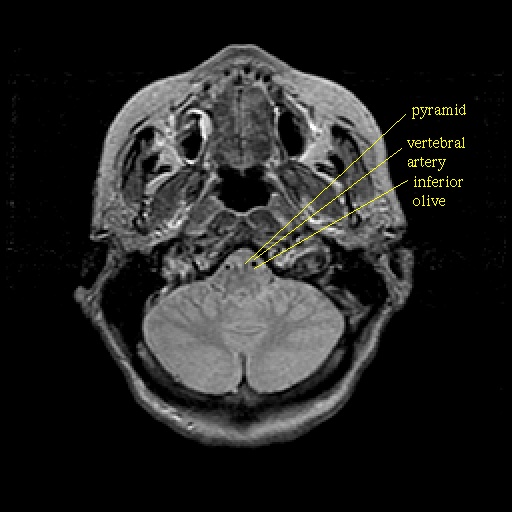

Proton density-weighted structural MR: Slice 9

Slice 9